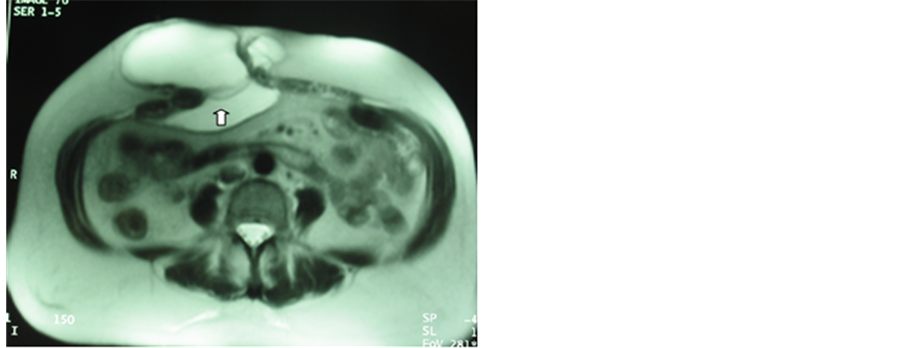

In the postoperative period, the first month control was especially useful to manage the immediate postoperative seroma: position, amount and relation with the mesh. In the axial and sagittal views it is possible to see the seroma between the skin and the mesh, behind the mesh inside the abdominal cavity, or both (Figures 2-4). Also, this approach allows to determinate the correct position of the mesh, the absence of relapsing and the relation with the intestinal content.

Three patients developed big-size seroma (30%) (Figures 2-4), but evacuation was not necessary.

Figure 2. One month postoperative sagittal MRI: control after laparoscopic surgery on a central incisional hernia. The arrow shows the correct position of the mesh and tacks. A big seroma appears inside the abdominal cavity.

Figure 3. One month postoperative axial MRI control after laparoscopic surgery on a middle-right flank incisional hernia. The arrow shows the mesh. The seroma appears both under the skin and inside the abdominal cavity.